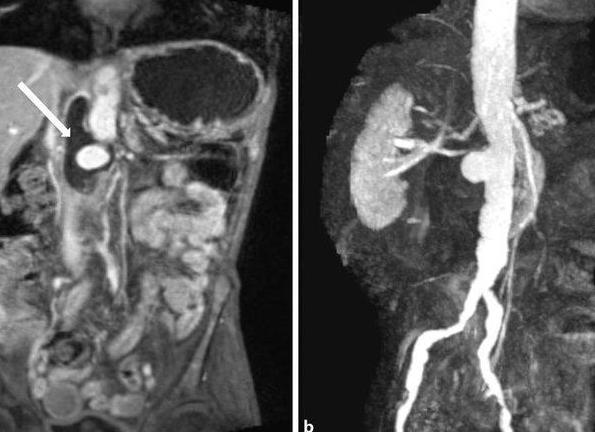

Наиболее современный метод диагностического обследования, который, в свою очередь, позволяет получить наиболее достоверную информацию не только о строении, но и о полной работе органа – МРТ. При помощи этого метода диагностического обследования, можно выявить нарушения не только в печени, но и в иных органах, например: мочевом пузыре, жёлчном пузыре, 12-перстной кишке и т.д.